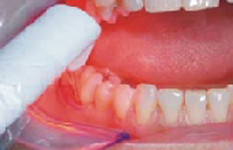

Přístroj na principu světlem aktivovaná desinfekce neboli fotodynamická antimikrobiální chemoterapie. Přístroj s okamžitým účinkem ničí veškeré mikroorganismy bez jakýchkoli vedlejších účinků. Jedná se o bezbolestné ošetření, které nevyžaduje anestezii, nemá vedlejší účinky a ničí 99% bakterií. Používá se především v parodontologii a implantologii při léčbě zánětů v okolí zubů a implantátů (dezinfekce tzv. chobotů), záchovné stomatologii (ošetření kazů) i endodoncii (dezinfekce kanálků zubu).